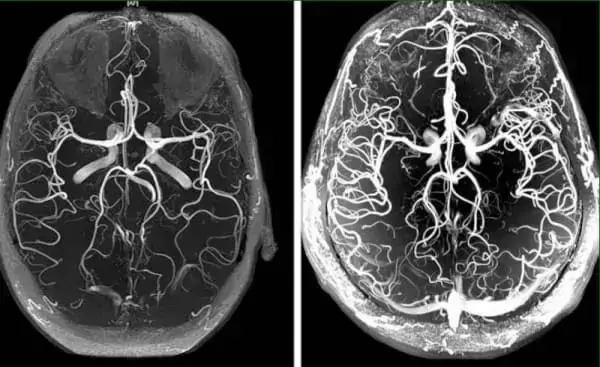

Многие годы вы можете не знать о своей болезни, не предъявлять жалоб, иметь высокую жизненную активность, хотя иногда могут случаться приступы «дурноты», выраженной слабости и головокружения. Но и тогда все полагают, что это от переутомления. Хотя именно в этот момент необходимо задуматься об артериальном давлении и его измерить. Гипертония может развиваться на протяжении многих лет, из-за этого ее называют «безмолвный убийца». Главным симптомом гипертонии является головная боль. Это происходит по причине сужения, спазма сосудов головного мозга.

Ангиодистония сосудов головного мозга – это патологическое состояние, при котором нарушается тонус сосудов и нормальное кровообращение в тканях головного мозга. В этой статье вы сможете прочитать про её причины, механизмы и симптомы, при которых пора бить тревогу. А также про грозные осложнения этого коварного заболевания и про современный подход к лечению, доступный каждому.

Ангиодистония сосудов головного мозга влияет на работоспособность всего организма. Из-за неадекватного кровоснабжения мозга, снижается общая работоспособность, появляется слабость, а важные системы организма начинают работать со сбоями.

В основе лечения кровообращения сосудов головного мозга лежит очищение сосудов всего организма от накопленных загрязнений. Холестериновых бляшек, тромбов и кальциевой извести.